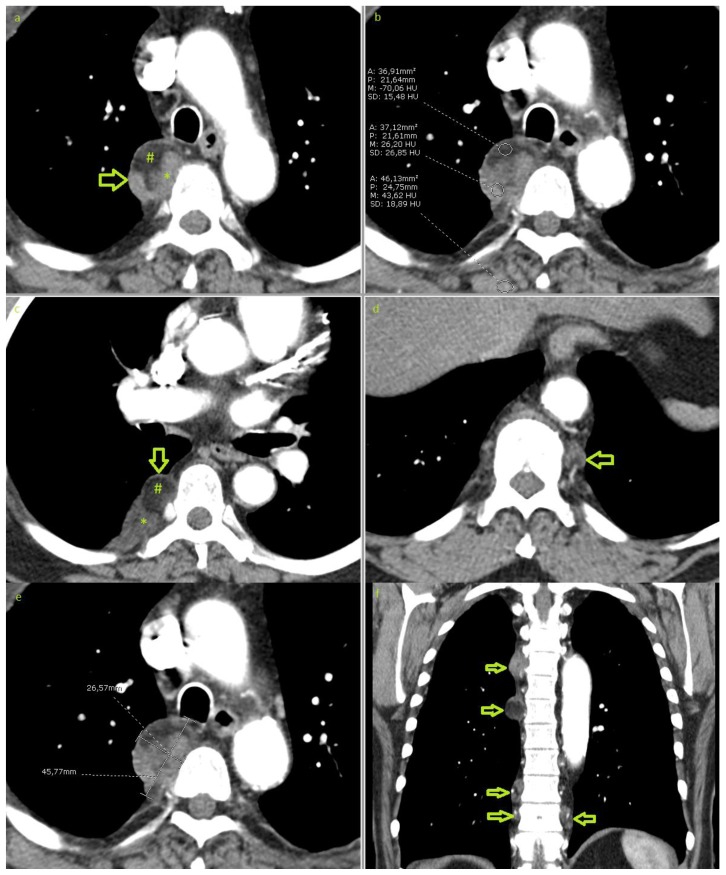

Figure 2.

70-year-old male with bilateral multifocal extra-adrenal myelolipoma. Contrast enhanced CT of the chest in an arterial phase demonstrating a well-circumscribed right paravertebral mass at the level of the aortic arch measuring 45×26×56mm(a & e). The mass shows mixed density, partially hypodense with −70 hounsfield units (b) due to fat content (#) and partially hyperdense due to myeloid tissue (*). Multiple smaller lesions are shown bilaterally (arrows in c, d & f). No infiltration of the neighbouring tissues. (Technique: 16-MDCT scanner, Automatic tube current modulation ranging between 131 and 250 mA, 120KVp. 5mm slice thickness. Soft tissue window, level/width: 15/350. i.v. injection of 60ml of 300mg/ml iodine concentration non-ionic contrast. a)–e) axial plane, (f) coronal reformation).